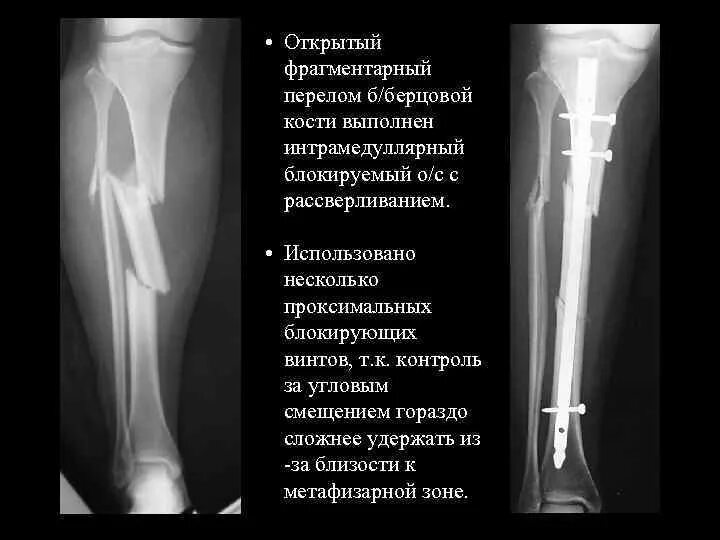

Перелом берцовых